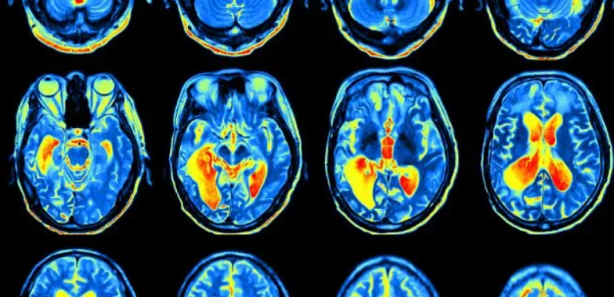

En çarpıcı ve korkutucu değişiklikler ise beyinde yaşandı. Doktorlar, Tulleken’in diyetten önceki ve sonraki beyin taramalarını karşılaştırdığında, diyet sonrasında beynin belirli bölgeleri arasında yeni fonksiyonel bağlantıların oluştuğunu gördü. Tulleken bu gelişmeyle ilgili olarak, “Diyet, beynimin ödül merkezini, tekrar eden, otomatik davranışları yönlendiren bölgelerle ilişkilendirdi. Yani bu yiyecekleri yemek, beynimin ben istemesem bile yapmamı söylediği bir şey hâline geldi” diyor.